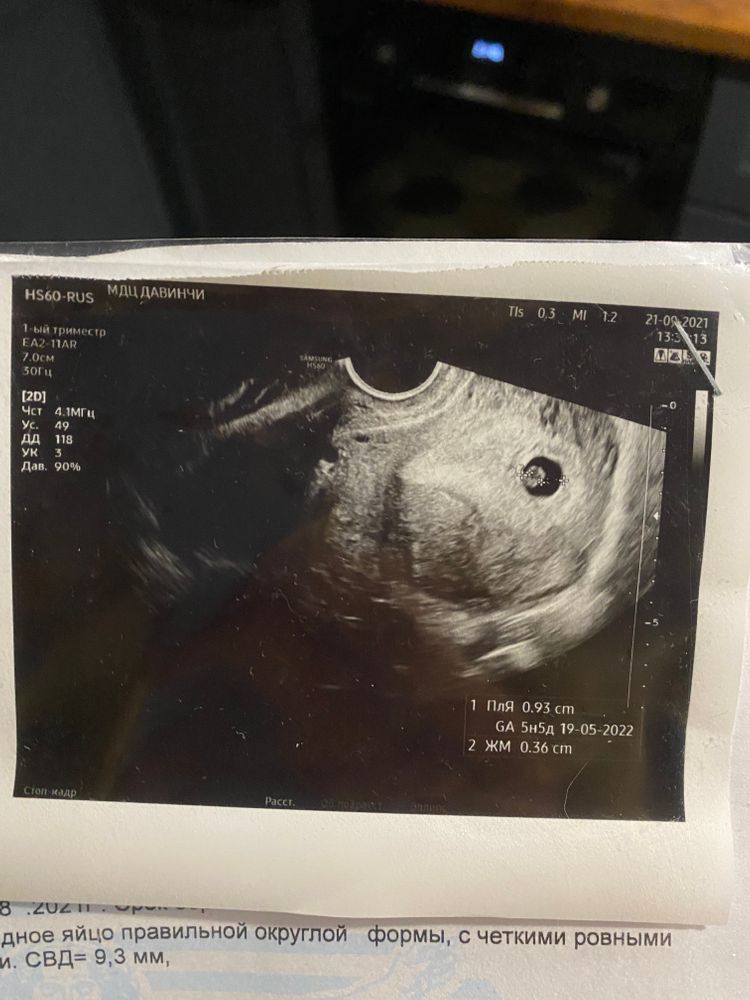

В чт будет уже 9 недель, но сердце не слушаем, но его отлично видно) обычно дают послушать на первом скрининге. Главное его увидеть, а слушать можно уже потом. У меня на 5.4 еще ничего не былл кроме ЖМ в ПЯ, через 6 дней сделала узи и там четко было видно эмбрион и масенькое сердечко.

Расулова Диля, да у меня по этому узи была 5-6 неделя, следовательно сейчас 6-7. Но по хгч все странно, да и обычно овуляцию фиксировали позднюю. Сегодня вот буду держать пальчики за хороший исход